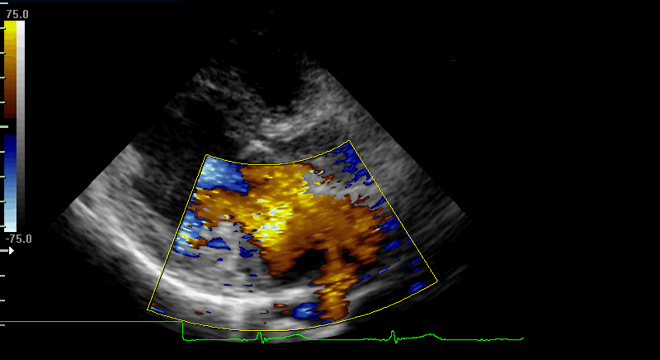

- Echokardiographie (Herzultraschall-Untersuchung)